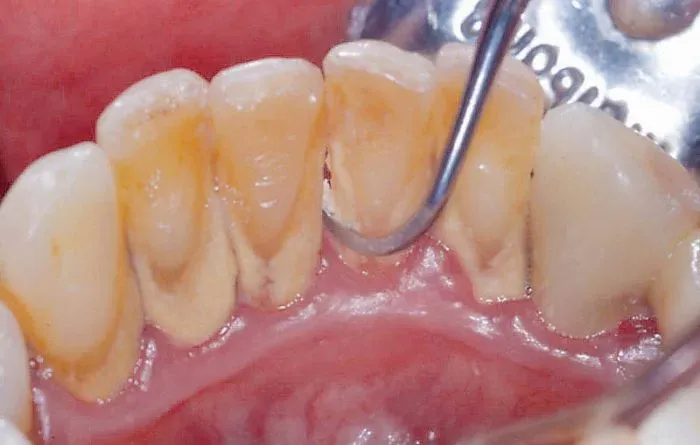

Cao răng (hay còn gọi là tartar, calculus) là những mảng bám cứng, xám hoặc vàng nâu bám chặt vào bề mặt răng, đặc biệt là gần đường viền nướu. Ban đầu, cao răng hình thành từ những mảng thức ăn thừa, vi khuẩn và khoáng chất trong nước bọt tích tụ trên răng. Nếu không được loại bỏ kịp thời bằng cách chải răng và sử dụng chỉ nha khoa thường xuyên, những mảng bám này sẽ dần bị vôi hóa, trở nên cứng và khó loại bỏ hơn rất nhiều.

Điều quan trọng cần hiểu là, cao răng không giống như mảng bám thông thường. Mảng bám mềm có thể dễ dàng loại bỏ bằng các biện pháp vệ sinh răng miệng hàng ngày, còn cao răng đã gắn chặt vào răng, đòi hỏi sự can thiệp của các phương pháp chuyên nghiệp.

- Cao răng trên nướu: Loại cao răng này thường có màu vàng hoặc cam, hình thành ở phần răng tiếp xúc với nước bọt và không khí. Cao răng trên nướu thường dễ nhìn thấy và có thể gây khó chịu khi chạm vào.

- Cao răng dưới nướu: Loại cao răng này có màu nâu sẫm hoặc đen, hình thành ở phần răng nằm dưới đường viền nướu. Cao răng dưới nướu khó phát hiện hơn và thường gây ra các vấn đề nghiêm trọng về nướu, như viêm nha chu.